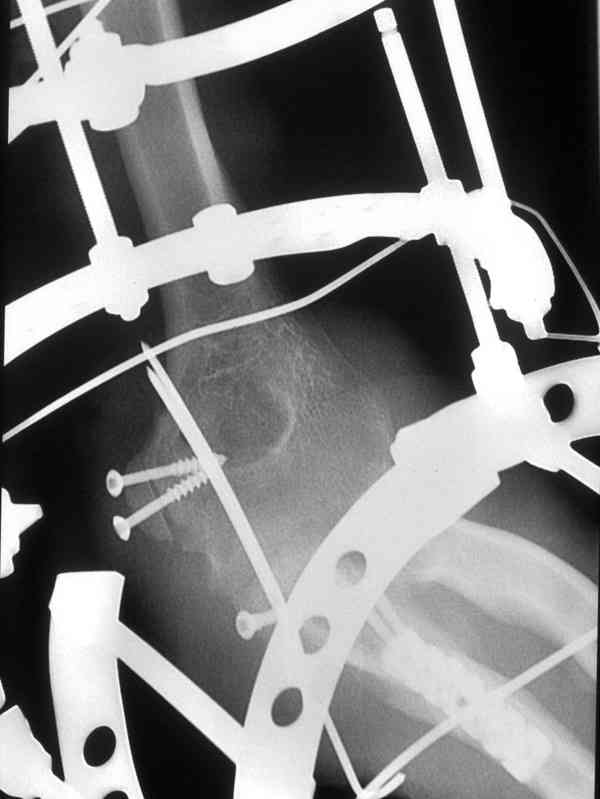

Больной был прооперирован.Протеза головки лучевой у нас нет. Решили с локтевой костью пока ничего не делать. Выполнили операцию по востановлению связочного аппарата локтевого сустава(см.схему)- модфикация метода W.E.Spring,сухожилие мы фикстровали к винту на локтевой.

Естественно ревизия сустава и удаление рубцово-хрящевидных тканей.Затем наложили аппарат Илизарова с шарнирами. Первые 2 дня сустав был фиксирован трансартикулярно 2-мя спицами, затем спицы удалили. И больной начинает движения в аппарате.

Прилагаюся послеоперационные рентгенограммы.

Что-то по снимкам ось шарниров с осью вращения локтевого сустава не сильно близко.